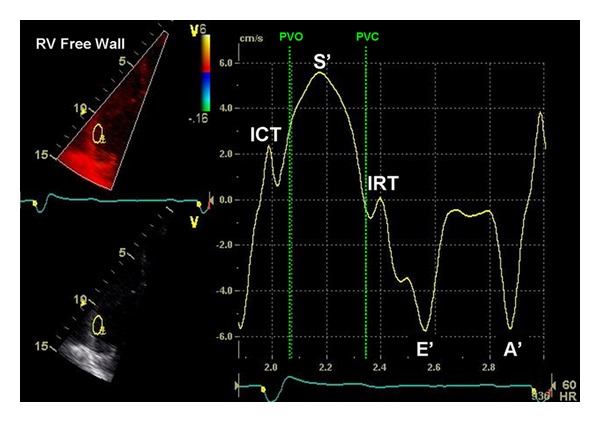

经胸超声心动图(TTE)是诊断和随访儿童和青壮年先天性心脏病(CHD)的一线工具。适当使用TTE可以减少对更多侵入性方式的需求,如心导管插入术和心脏磁共振成像。最近出现了新的超声心动图技术:组织多普勒成像,组织跟踪(应变和应变率),矢量速度成像(VVI),心肌性能指数,等容积加速(IVA)期间的心肌加速,收缩期与舒张期持续时间之比(S/D比),以及收缩期右心室(RV)功能的二维测量(如三尖瓣环平面收缩位移,TAPSE)。这些可能成为心室功能、顺应性和疾病进展的有价值的指标。此外,用于评估瓣膜功能、装置位置和心室容积的三维超声心动图正在被纳入常规临床护理。本文就这些超声心动图技术在冠心病患者中的潜在应用和局限性进行了讨论。特别关注的是超声心动图评估与右心室容量增加(如法洛四联症修复后的肺反流)或儿童和年轻人压力(如肺动脉高压)相关的右心室(RV)功能。

Transthoracic echocardiography (TTE) is the first-line tool for diagnosis and followup of pediatric and young adult patients with congenital heart disease (CHD). Appropriate use of TTE can reduce the need for more invasive modalities, such as cardiac catheterization and cardiac magnetic resonance imaging. New echocardiographic techniques have emerged more recently: tissue Doppler imaging, tissue tracking (strain and strain rate), vector velocity imaging (VVI), myocardial performance index, myocardial acceleration during isovolumic acceleration (IVA), the ratio of systolic to diastolic duration (S/D ratio), and two dimensional measurements of systolic right ventricular (RV) function (e.g., tricuspid annular plane systolic excursion, TAPSE). These may become valuable indicators of ventricular performance, compliance, and disease progression. In addition, three-dimensional (3D) echocardiography when performed for the assessment of valvular function, device position, and ventricular volumes is being integrated into routine clinical care. In this paper, the potential use and limitations of these new echocardiographic techniques in patients with CHD are discussed. A particular focus is on the echocardiographic assessment of right ventricular (RV) function in conditions associated with increased right ventricular volume (e.g., pulmonary regurgitation after tetralogy of Fallot repair) or pressure (e.g., pulmonary hypertension) in children and young adults.